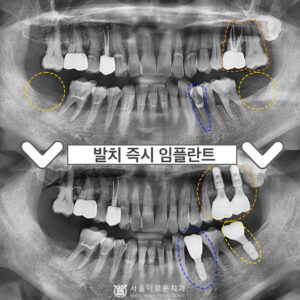

부천중동치과 발치 즉시 임플란트를 하고 싶다면? 안녕하세요 😀 이에 좋은, 이로움을 알리는 서울 이로운 치과입니다. 오늘은 ‘발치즉시 임플란트’에 대해 소개해드리려 합니다. ^^ 발즉 임플란트란? 당일 발치 후 바로 임플란트를 식립하는…